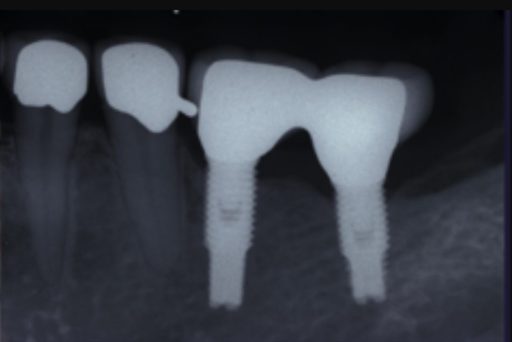

| 主訴 | 全顎治療希望、歯が無いので噛みずらい。定年で時間の余裕出来たので、インプラントで治療して欲しい。 |

| 治療内容 | プラークコントロール不良なため歯周治療を行い、残存歯を極力温存し、欠損部インプラントを施し咬合再構成を行う。 プロビジョナルレストレーションによる咬合関係を模索した後、全顎にわたりセラミックによる補綴治療、その後メインテナンスに移行 |

| 治療費 | 6,470,000円(税込)(インプラントすべて含む) |

| 治療期間 | 1年6ヶ月 |

| 治療回数 | 72回 |

| 想定されたリスク | 食いしばり(パラファンクション)によるセラミックの破折、歯の破折 |